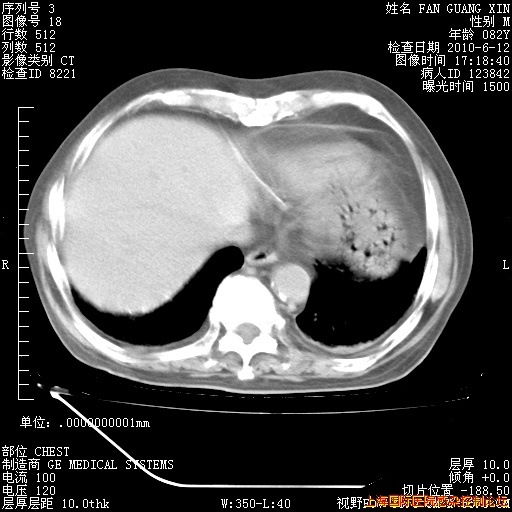

补发6月12日肺部CT肺窗

6月12日肺窗

6月12日纵膈窗

整整相隔30天的肺部CT好像有所好转啊。甲强龙减量第3天,需要观察体温。

海管,自昨日你和我通完话后,不知您岳父消化道症状有无缓解?体温怎样?阅读7.12日胸部ct,个人认为目前激素治疗是有效的,甲强龙减量是适宜的。因在抗痨治疗,需密切观察肝功、肾功能和血常规。不过,老年、长期住院和大量使用激素,很担心菌群失调发生